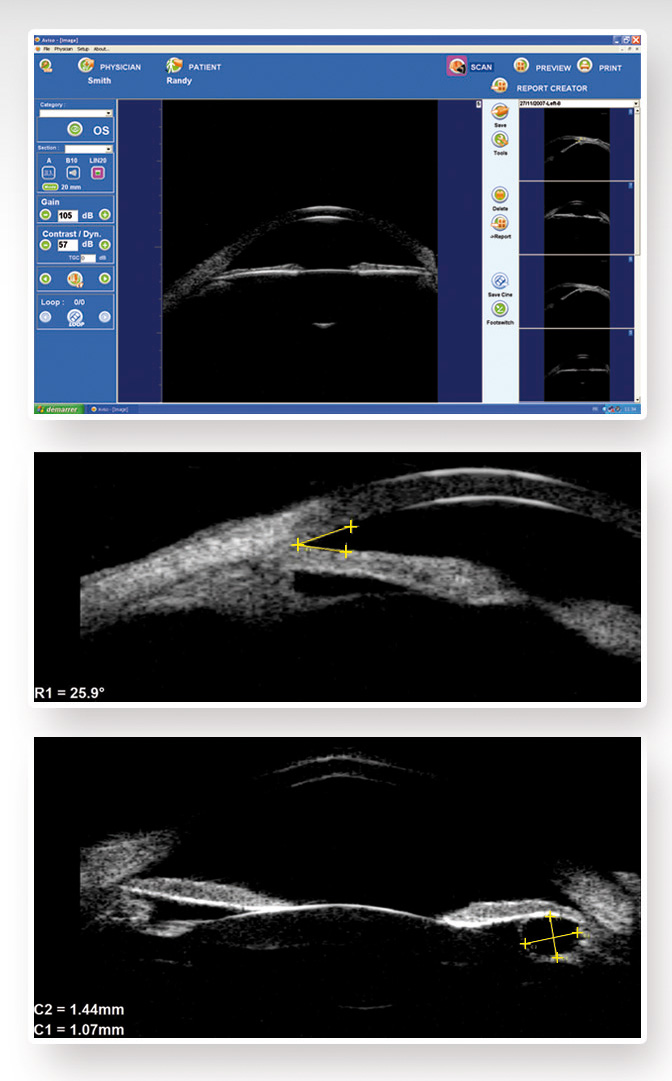

AVISO AB ULTRASON & UBM

Reflex UBM gözün antrerior ve posterior görüntülerini almak üzere B mod özelliklidir.